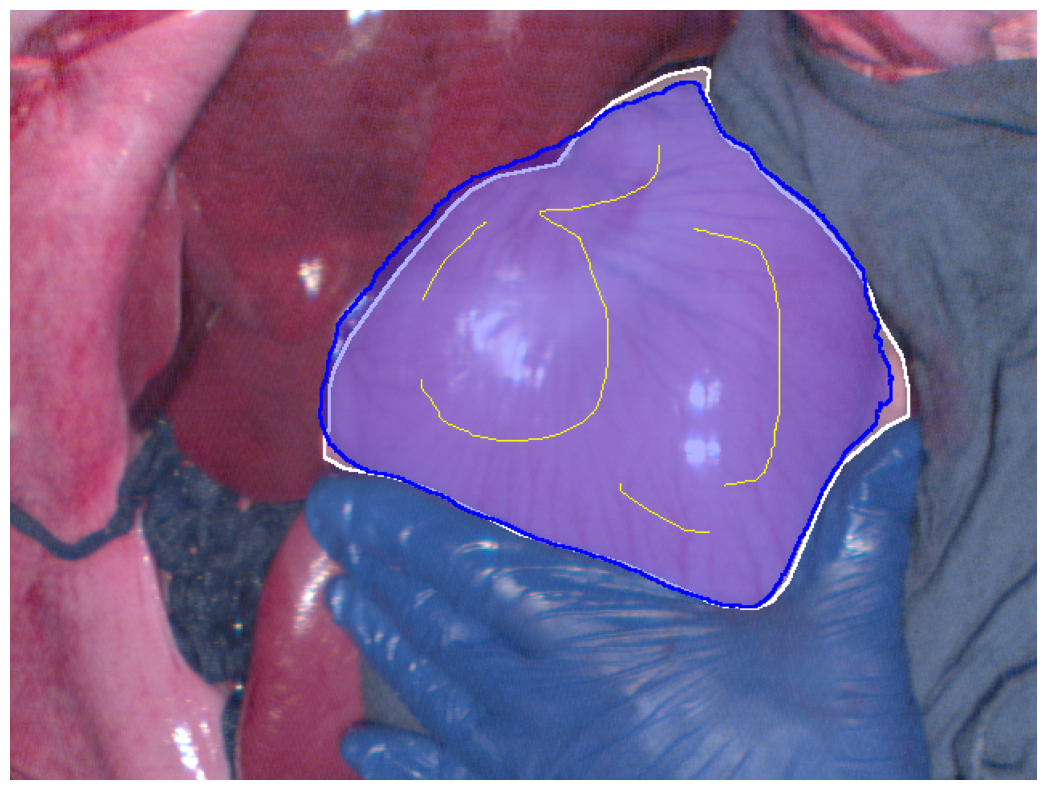

After generating the geodesic distance map, it is normalized to a range of 0 to 1. A binary classification is generated according to the user-controlled threshold, where pixels with geodesic distance values below the threshold are labelled as part of the region of interest. The user can adjust the threshold value to extend the scribbles into an appropriate segmentation result. In Fig. 1e, the white region represents the ground truth (indicating a pig’s stomach), while the blue region shows the segmentation result when the threshold is adjusted to achieve the maximum Dice coefficient. The user can also lower the threshold to obtain a more conservative segmentation result. This method is very flexible and also reduces the user’s annotation workload.

Figure 2: Segmentation results (blue regions) at the best Dice coefficient for different methods and ground truth (white regions), along with the curves of Dice coefficient variation with threshold adjustments.

In Fig. 2, the segmentation results at the best Dice for the four different methods are displayed, along with the variation in Dice coefficients with threshold adjustments. From Fig. 2e, it can be seen that the Euclidean distance method has the lowest maximum Dice score of 0.914. The methods using geodesic distance maps generated from hyperspectral images and reconstructed RGB images achieve similar maximum Dice values, both higher than the Euclidean method. The deep learning-based feature geodesic distance map method achieves the highest maximum dice coefficient.